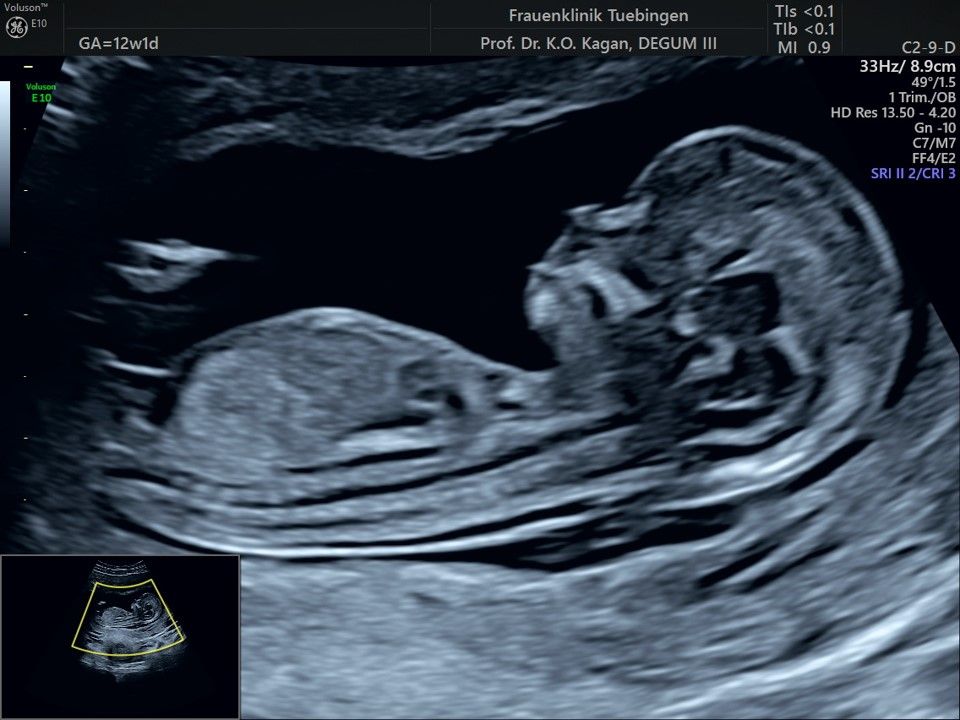

Im Rahmen des Ersttrimester-Screenings untersuchen wir die Organe des Feten mittels Ultraschall. Dabei machen wir auch gerne ein Bild für Sie.

Obwohl der Fet zu diesem Zeitpunkt erst zwischen 5 und 8cm groß ist, lassen sich bereits etwa die Hälfte aller schwerwiegenden Fehlbildungen erkennen bzw. ausschließen. Sollten wir eine Auffälligkeit sehen, werden wir mit Ihnen den Befund und das weitere Vorgehen ausführlich besprechen.

Die eigentliche Organuntersuchung findet um die 20.SSW (zweites Screening) statt. Das Ersttrimester-Screening und das zweite Screening sind sich ergänzende Untersuchungen und ersetzen sich gegenseitig nicht.